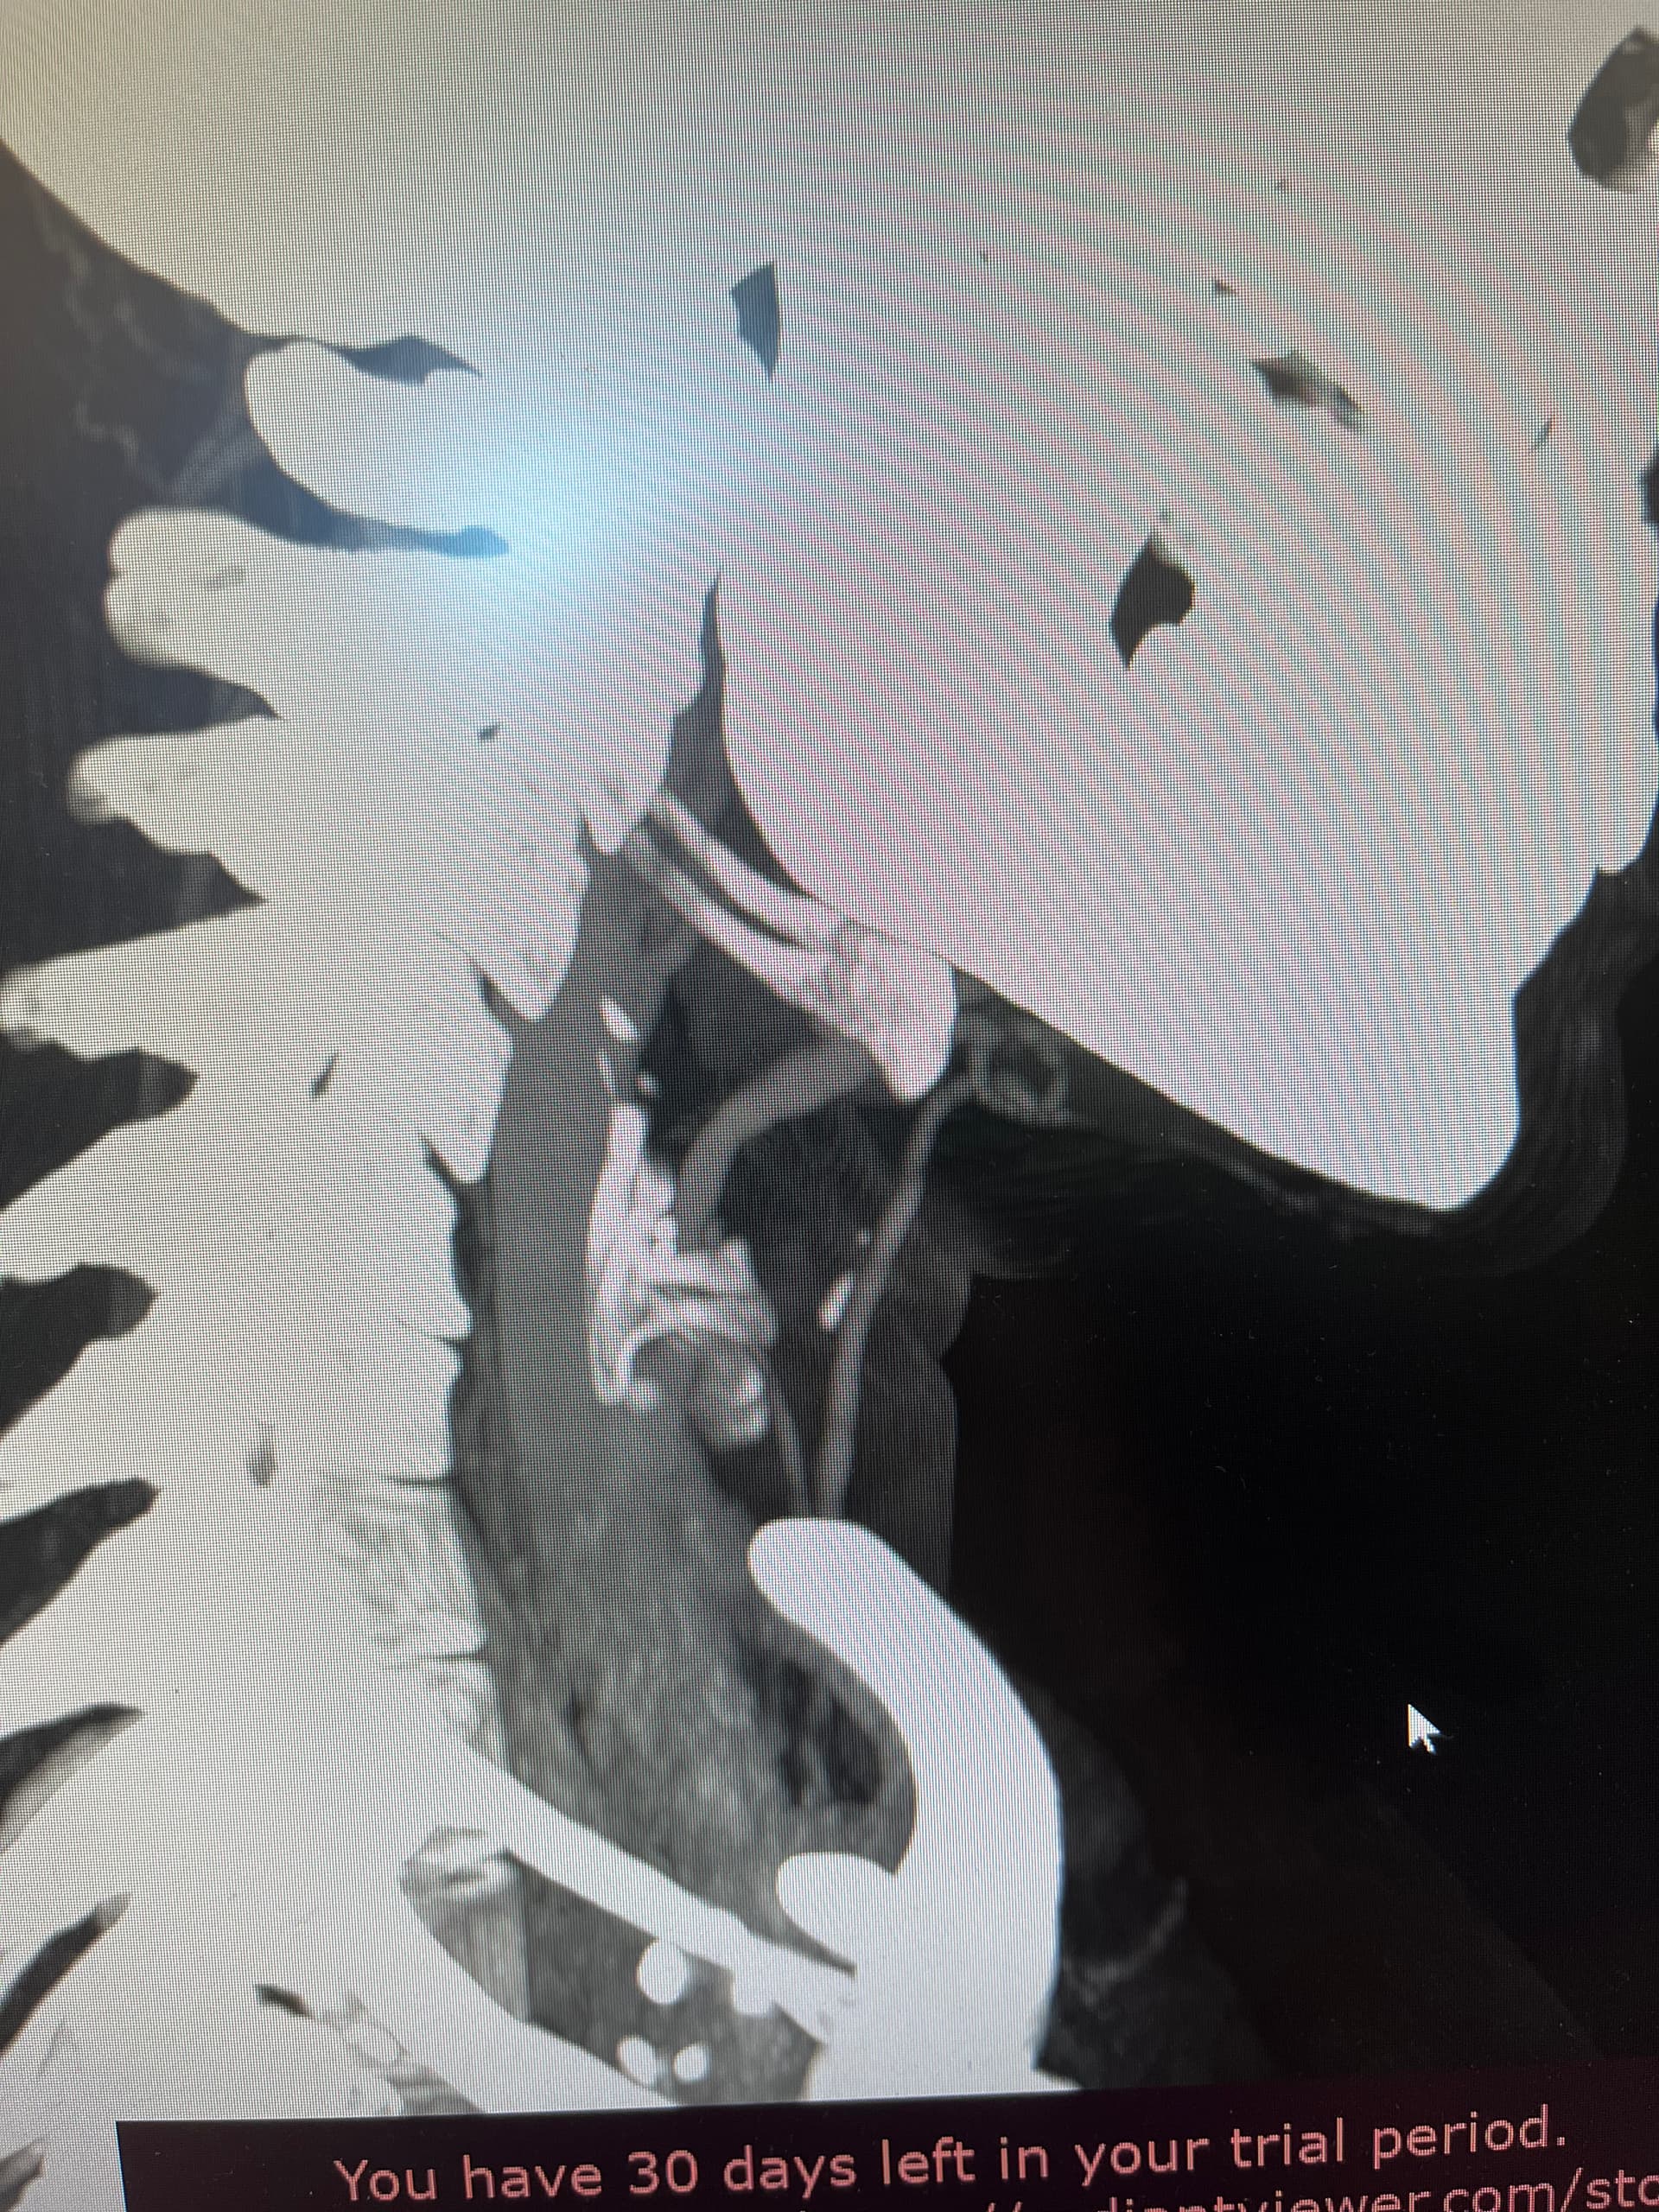

Might want to check out left styloid process and ligament also. Can see it on the 3D but not all of it due to blood vessels. Might be contributing to the hyoid injury/problem if ligament is calcified.

Hi, I’m so sorry for the delay in replying to you, we had some family stuff come up and this got pushed to the back burner for awhile. I’ve gone back a few frames, am I getting closer? I can also send you the whole CT if that would make things easier. I’m sorry, I’m not good with technology. I appreciate you taking the time to respond! Since we last spoke, I’ve developed a lot of neurological symptoms and weird physical ones like dizziness, headaches, brain fog, weird throbbing in my neck and head, can this all be tied in with hyoid bone problems? Thank you so much for your time!

Hi, good catch! I do have an elongated styloid on the left side too. And calcification on my ligaments as well, per my ct report. I’ve been wondering how much that plays into what’s going on now. I felt a lot of relief from the poking after my first styloidectomy, so I had decided to wait on my second one for awhile, then this injury happened.